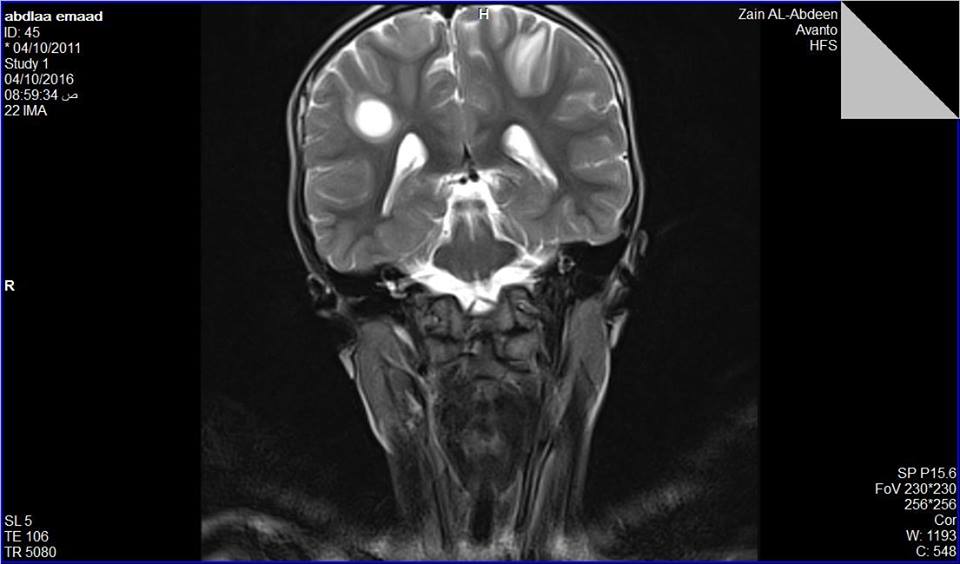

تمكن أخصائيي أمراض الأطفال والأمراض العصبية في مستشفى الإمام زين العابدين عليه السلام، التابع للعتبة الحسينية المقدسة، من معالجة طفل من محافظه دهوك مصاب بالتهاب الدماغ والنخاع المنتشر المتكرر، بالعلاج الوريدي والعلاج الفموي، وبدون تداخل جراحي. وذكر الإعلامي في مستشفى الإمام زين العابدين عليهم السلام مصطفى الموسوي لوكالة نون الخبرية، بأنه ادخل الطفل (ع.ع - عمره خمس سنوات وشهرين) من محافظه دهوك في قسم الأطفال في مستشفى الإمام زين العابدين عليه السلام، وكان يعاني ضعف عضلي مترقي واضطراب بالمشي (عدم ثبات وسقوط) بحسب رئي الأطباء. فيما بين اختصاصي الأمراض العصبية د.بشار زهيرة واختصاصية أمراض الأطفال د.سندس خضر المشرفين على علاج الطفل، بأنه بعد إجراء الاستقصاءات الشعاعية والمخبرية اللازمة، بين التصوير بالرنين المغناطيسي ثلاث بؤر مزيلة للنخاعين (اثنان بنصف الكرة المخية الأيمن وواحدة في نصف الكرة المخية الأيسر)، إن هذه حالة تعتبر سريرية ونادرة وتم استبعاد جميع الحالات التي تدخل بالتشخيص التفريقي. وأضاف اختصاصي العصبية والأطفال بأنه تم العلاج الطفل وريديا لمدة ستة أيام بالمستشفى وحدث تحسن سريري دراماتيكي، حيث اخرج بعدها من المستشفى معتمدا على العلاج الفموي لمدة ثلاثة أشهر مع التوصيات الطبية الخاصة وتم إجراء أعادة لصورة الرنين المغناطيسي بعد ثلاثة أشهر وحالياً الطفل بحالة عامة جيدة ولا يعاني من أي ضعف عضلي ونشاطه الفيزيائي طبيعي. وحول هذا المرض بين الأطباء الاختصاصيين، إن هذا المرض ينتج عن التهاب الدماغ والنخاع المنتشر الحاد آفات التهابية متعددة تصيب الدماغ والنخاع الشوكي، وخاصةً المادة البيضاء في الجهاز العصبي المركزي،وتوجد معظم هذه الآفات عادةً في المادة البيضاء الوسطى وتحت القشرية والمَوصِل القشري الأبيض والرمادي في كُلٍّ من نصف الكرة المخية والمخيخ وجذع الدماغ والنخاع الشوكي كذلك قد تهاجم المادة البيضاء المحيطة بالبطين، وفي حالة تعرض المريض لأكثر من نوبة من زوال الميالين، يُسمى المرض في هذه الحالة التهاب الدماغ والنخاع المنتشر المتكرر أو التهاب الدماغ والنخاع المنتشر متعدد الأطوار (MDEM)، وان نسبة انتشار المرض على مستوى العالم يصل إلى (8) أشخاص من كل مليون نسمة سنويًا. محسن الحلو خاص بوكالة نون الخبرية